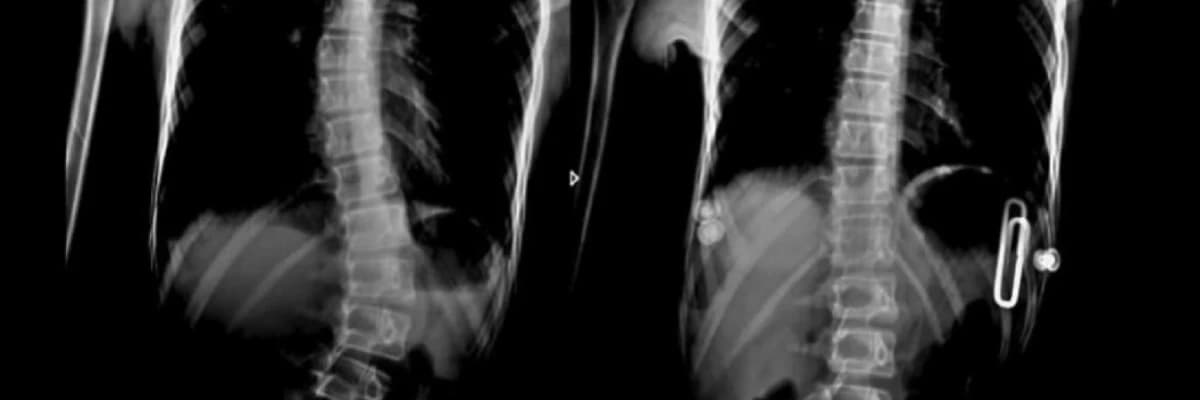

Skolyozda braket müalicəsi